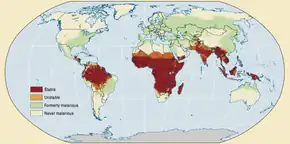

The WHO estimates that in 2021 there were 247 million new cases of malaria resulting in 619,000 deaths.[5] Children under 5 years old are the most affected, accounting for 67% of malaria deaths worldwide in 2019.[192] About 125 million pregnant women are at risk of infection each year; in Sub-Saharan Africa, maternal malaria is associated with up to 200,000 estimated infant deaths yearly.[30] Since 2015, the WHO European Region has been free of malaria. The last country to report an indigenous malaria case was Tajikistan in 2014.[5] There are about 1300–1500 malaria cases per year in the United States.[26] The United States eradicated malaria as a major public health concern in 1951,[193] though small outbreaks persist.[194] Locally acquired mosquito-borne malaria occurred in the United States in 2003, when eight cases of locally acquired P. vivax malaria were identified in Florida, and again in May 2023, in four cases, as well as one case in Texas,[195] and in August in one case in Maryland.[196] About 900 people died from the disease in Europe between 1993 and 2003.[70] Both the global incidence of disease and resulting mortality have declined in recent years. According to the WHO and UNICEF, deaths attributable to malaria in 2015 were reduced by 60%[79] from a 2000 estimate of 985,000, largely due to the widespread use of insecticide-treated nets and artemisinin-based combination therapies.[76] Between 2000 and 2019, malaria mortality rates among all ages halved from about 30 to 13 per 100,000 population at risk. During this period, malaria deaths among children under 5 also declined by nearly half (47%) from 781,000 in 2000 to 416,000 in 2019.[77]

Malaria is presently endemic in a broad band around the equator, in areas of the Americas, many parts of Asia, and much of Africa; in Sub-Saharan Africa, 85–90% of malaria fatalities occur.[197] An estimate for 2009 reported that countries with the highest death rate per 100,000 of population were Ivory Coast (86.15), Angola (56.93) and Burkina Faso (50.66).[198] A 2010 estimate indicated the deadliest countries per population were Burkina Faso, Mozambique and Mali.[199] The Malaria Atlas Project aims to map global levels of malaria, providing a way to determine the global spatial limits of the disease and to assess disease burden.[200][201] This effort led to the publication of a map of P. falciparum endemicity in 2010 and an update in 2019.[202][203][204] As of 2021, 84 countries have endemic malaria.[5]

The geographic distribution of malaria within large regions is complex, and malaria-afflicted and malaria-free areas are often found close to each other.[205] Malaria is prevalent in tropical and subtropical regions because of rainfall, consistent high temperatures and high humidity, along with stagnant waters where mosquito larvae readily mature, providing them with the environment they need for continuous breeding.[206] In drier areas, outbreaks of malaria have been predicted with reasonable accuracy by mapping rainfall.[207] Malaria is more common in rural areas than in cities. For example, several cities in the Greater Mekong Subregion of Southeast Asia are essentially malaria-free, but the disease is prevalent in many rural regions, including along international borders and forest fringes.[208] In contrast, malaria in Africa is present in both rural and urban areas, though the risk is lower in the larger cities.[209]